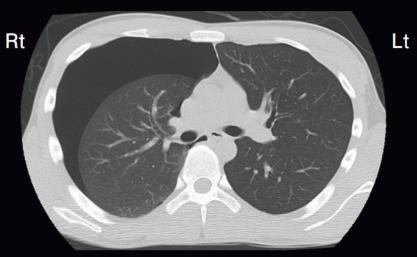

Aさん(27歳、男性)は、突然の胸痛と呼吸困難があり、救急外来を受診した。

意識は清明。身長179cm、体重63kg、胸部は平である。20歳から1日50本の喫煙をしている。バイタルサインは、体温36.1°C、呼吸数 22/分、経皮的動脈血酸飽和度(SpO2)96%(room air)である。

胸部CT(別冊No. 2)を示す。

Aさんの所見から考えられるのはどれか。